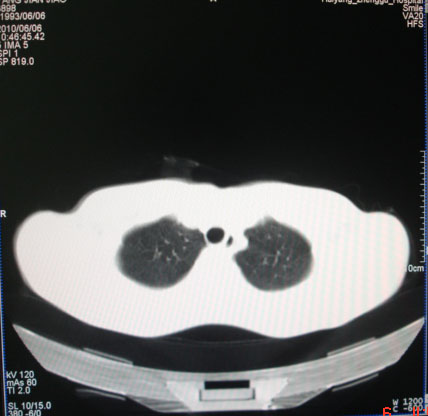

标题: CT26938:单发肺窗

病人17岁。咳嗽伴血丝痰2年?外院x片示左上肺椭圆形影,疑胸腺瘤

左肺尖见占位,建议上传纵隔窗及向上扫描。

左上纵隔占位性病变?